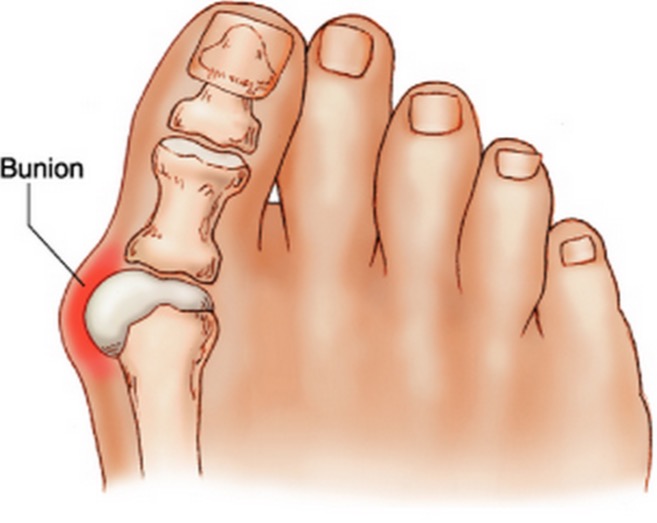

Ef þú ert með bólginn hnúð þar sem stóra táin byrjar og finnur oft til ertu líklegast með Bunion, en ég fann ekkert íslenskt orð fyrir þetta.

Ég rakst á þessa uppskrift af drykk sem á að draga úr þessum bólgum og létta á sársaukanum í fótunum.

Uppskrift:

300 ml vatn

1 msk af muldum lárviðarlaufum

Best er að útbúa þennan drykk að kvöldi til. Sjóðið þetta tvennt saman í 5 mínútur og geymið í pottinum yfir nótt. Sigtaðu vökvann frá og taktu af honum litla sopa yfir daginn. Ekki drekka hann allan í einu. Gerðu þetta í 3 daga í röð og útbúðu drykkinn alltaf að kvöldi. Eftir viku skaltu svo endurtaka þetta í þrjá daga.

Það kemur þér örugglega á óvart hversu mikið þú þarft að pissa meðan þú ert að drekka þennan drykk. Það sýnir að saltið í líkamanum er að leysast upp og getur valdið tíðum þvaglátum.

Þú ættir að finna fyrir miklum mun eftir 10 daga og þér mun líða mun betur. Gerðu þetta í tvo mánuði og hnúðurinn mun á endanum hverfa.

Að lokum skaltu mylja 5 lárviðarlauf og blandaðu þeim saman við 100 ml af 96% alkóhóli/spritti. Leyfðu þessu að bíða í viku og sigtaðu svo vökvann frá. Hann á svo að bera á hnúðinn. Til að fá sem bestu virknina farðu þá í fótabað (3 l vatn og matskeið af matarsóda) áður en þú berð þetta á. Þurrkaðu fæturnar, berðu lausnina á og farðu í bómullarsokka.

Eins og með öll mín svona „nornaráð“ þá ætla ég að taka það fram að ég er enginn læknir og þetta mál hefur ekki verið rannsakað af fagfólki. Hinsvegar hef ég gaman að því að prófa svona sjálf og ef þetta virkar, þá er það bara plús.